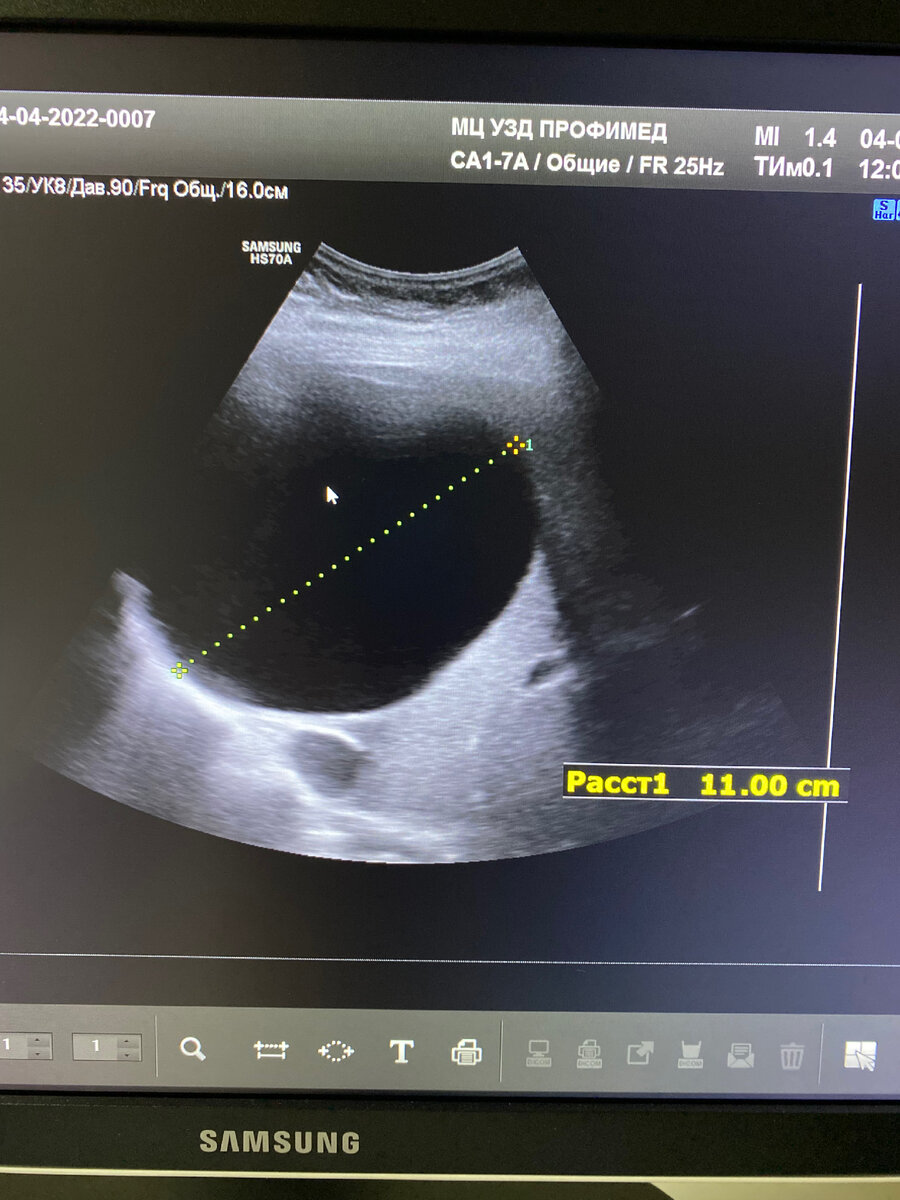

🔴Пациентка 76 лет, с жалобами на ноющие боли в правом подреберье.

🔴На узи органов брюшной полости в печени видим большое полостное образование d 11 см-солитарная киста.